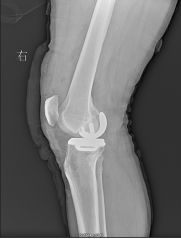

单髁置换术后X片

近日,常德市第二人民医院骨科成功为一例右膝重度骨关节炎患者完成了膝关节内侧单髁置换术,实施了小切口下对膝关节病变部位精准治疗的部分膝关节置换术。目前患者已康复出院。

骨科主任汪立波、副主任医师曾凡瑞通过详细的体格检查、结合影像学资料,综合评估病情后认为患者为右膝内侧间室骨性关节炎,外侧间隙关节软骨尚完好,且膝关节前后交叉韧带及内外侧副韧带均完好,患者年龄只有55岁,若行全膝关节置换为时尚早,且全膝关节置换手术需切除患者完好的外侧间隙关节软骨及正常的交叉韧带,虽能缓解疼痛,但关节功能会受到很大的影响。

通过与王叔叔及其家人详细的沟通后,决定为其行“右膝内侧单髁关节置换术”,王叔叔一家欣然接受了手术方案。手术顺利进行,术后第二天患者即下床活动,疼痛及关节功能明显改善。